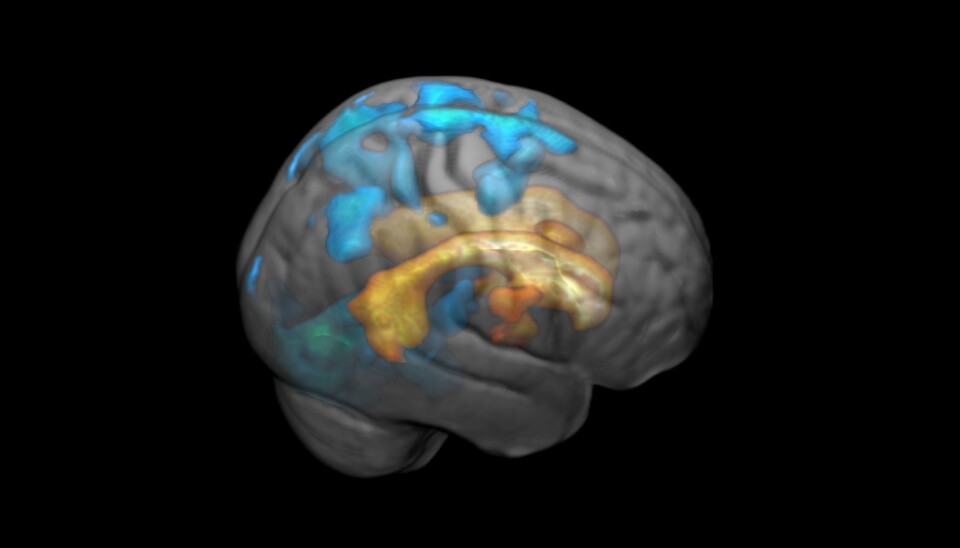

The effects of the white spots increase in volume as they spread across the surface of the brain. Here marked in blue

If you get scarring in your brain’s white matter, it is easy to grasp that it will affect exactly that area where the scar is. What Håberg and her colleagues found was that completely different parts of the brain are also affected by the scarring.

Including areas far removed from the scarred tissue.

“The effects of the white spots spread across the surface of the brain and increase in volume,” says Håberg.